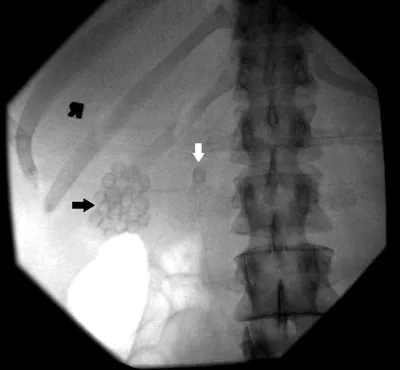

The next step is to obtain a GI consultation for a possible ERCP. This is arranged for the next day. The image shown in Figure 2 is obtained during the procedure.

Figure 2.

Describe what you see and read on

A fluoroscopic scout view of the right upper quadrant is obtained prior to the endoscopic procedure. Numerous stones are present in the gallbladder (black arrow). In addition, a solitary stone is seen outside the expected location of the gallbladder (white arrow), suggesting a stone in the biliary tree. A fluoroscopic image is obtained during the ERCP (Figure 3).